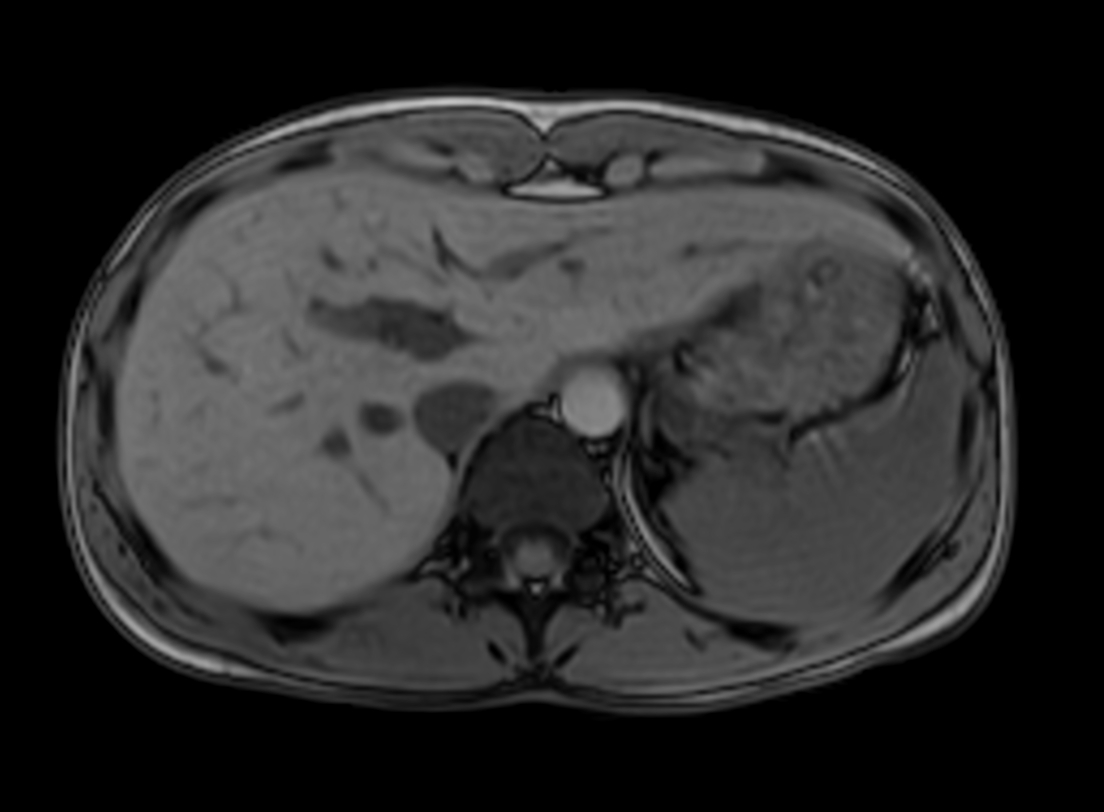

Axial mDIXON XD - T1w FFE (Water only)

Axial mDIXON XD - T1w FFE (In Phase)

Axial mDIXON XD - T1w FFE (Out Phase)